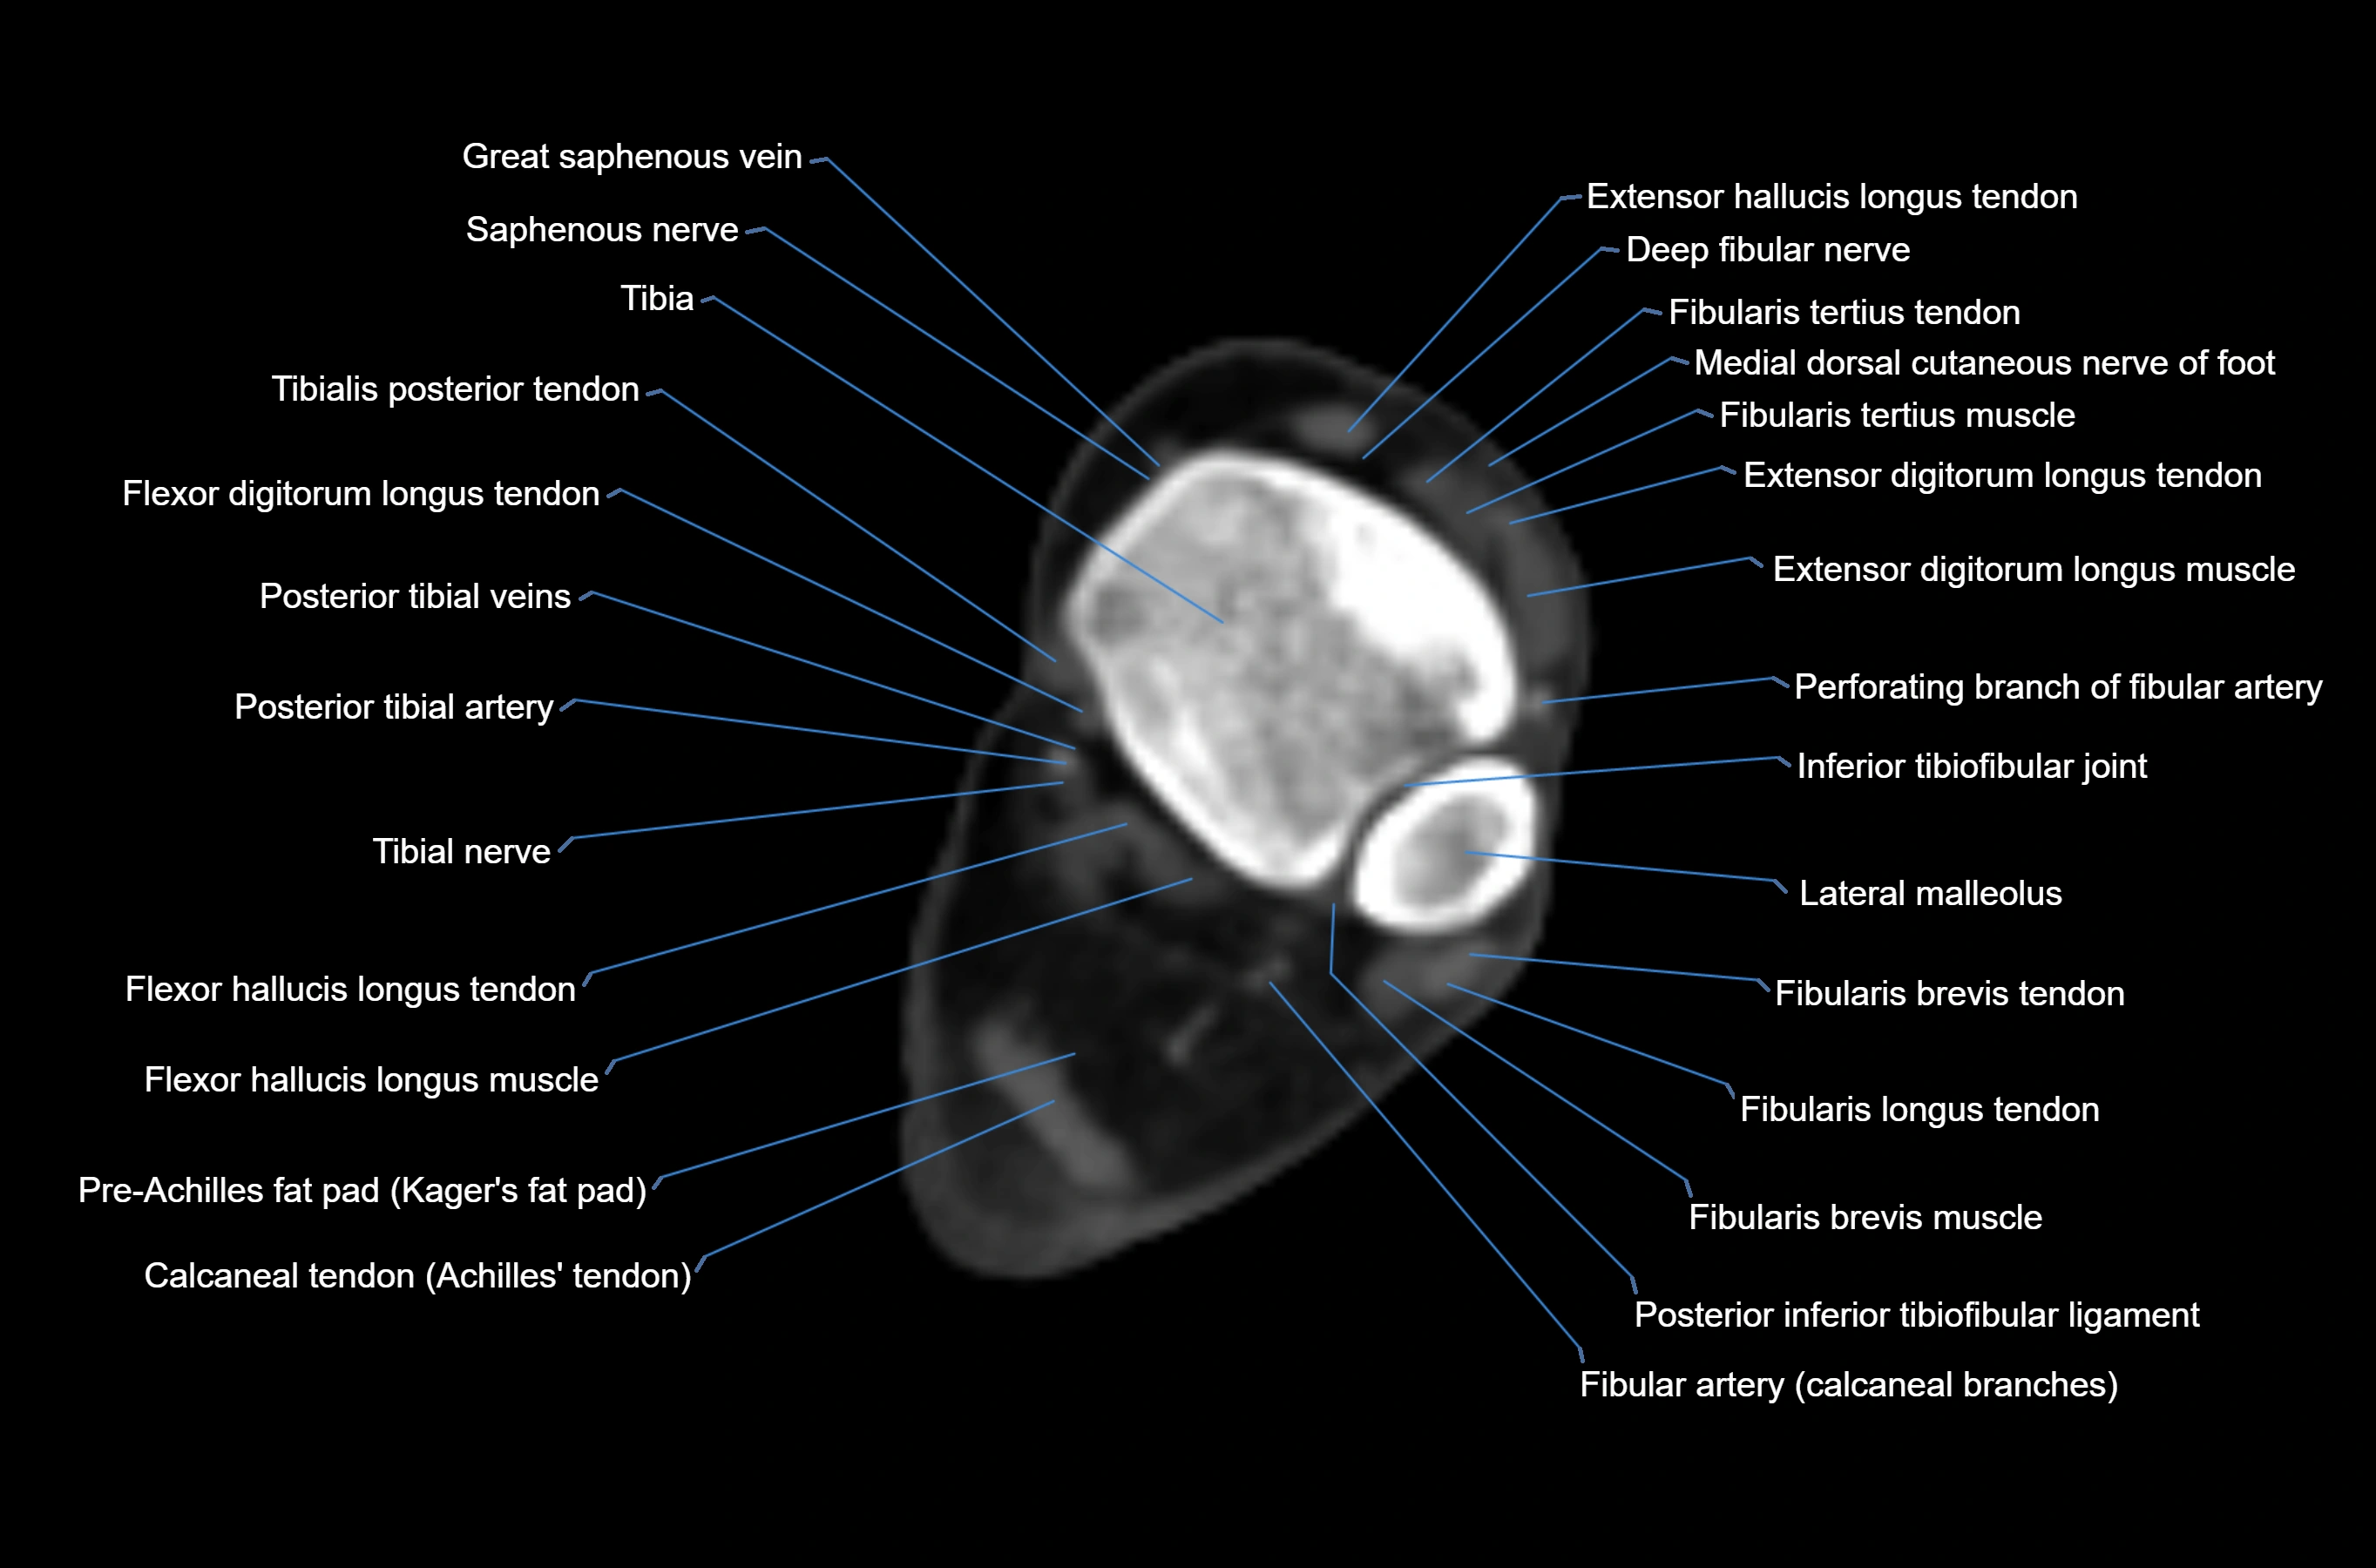

CT image